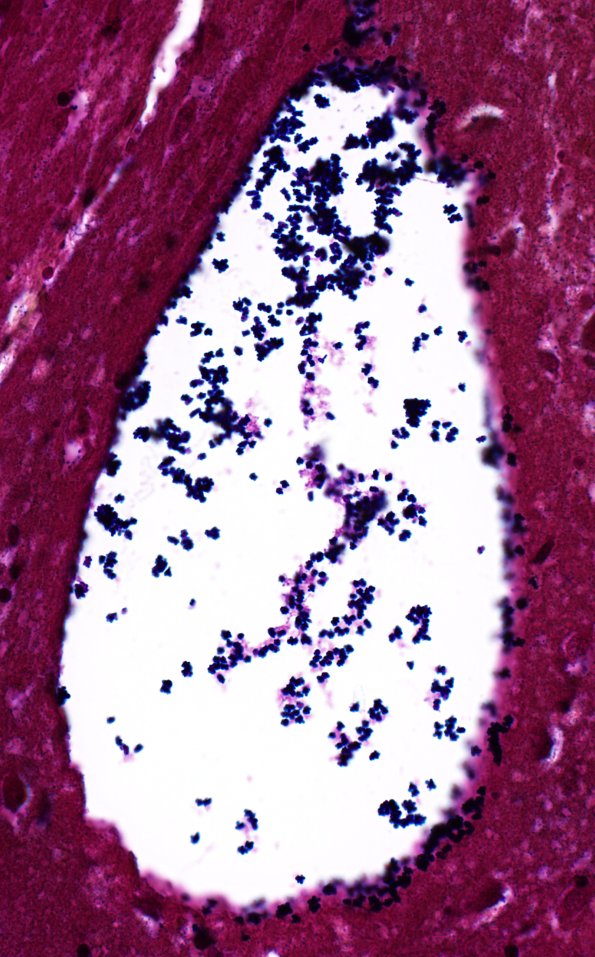

34C2C Swiss Cheese Brain (Case 12) Gram 40X 4

Bacteria are found in the vasculature and at the margins of the cysts. (Gram)